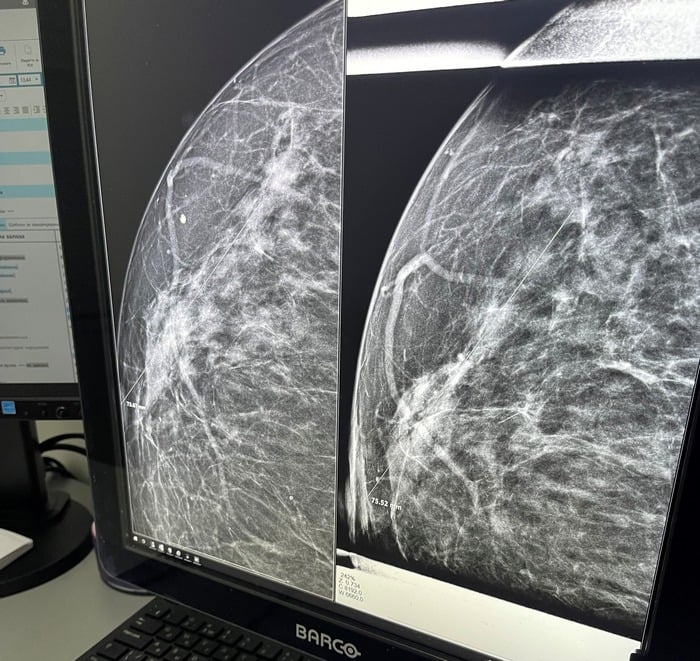

Найбільша небезпека для грудей — відсутність контролю над їхнім здоров'ям. Без самообстеження раз на місяць у домашніх умовах і щорічного відвідування мамолога неможливо дізнатися про наявність багатьох захворювань молочних залоз на їхніх ранніх стадіях розвитку, оскільки найчастіше вони безсимптомні. Так, на відміну від маститу, який одразу проявляється болем, почервонінням, лихоманкою, рак грудей може місяцями ніяк не давати про себе знати. Хоча за допомогою УЗД або мамографії він вже може бути виявлений.